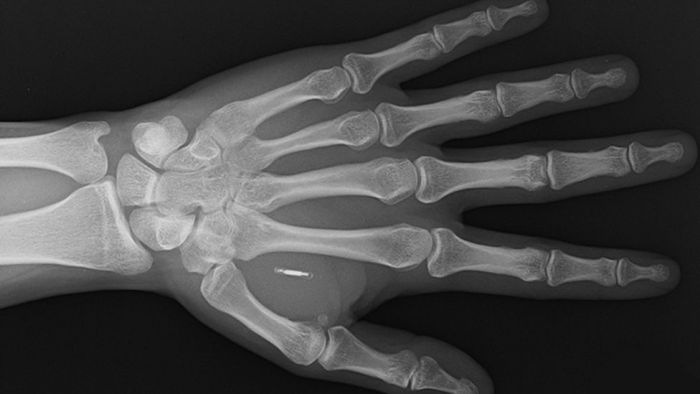

Bunun nedeni, 37 yaşındaki Paumen’ın ödeme yapmak için banka kartı veya cep telefonu kullanmasına gerek olmaması. Bu işlemlerin yerine, sol elini temassız kart okuyucunun yanına koyarak ödemelerini gerçekleştiriyor.

2019'da derisinin altına temassız bir ödeme mikroçipi enjekte edildiği için elini kullanarak ödeme yapabiliyor.

Walletmor'un çipi, bir gramdan daha hafif ve bir pirinç tanesinden biraz daha büyük küçük bir mikroçip; plastiğe benzer doğal kaynaklı bir malzeme olan biyopolimer içine yerleştirilmiş bir antenden oluşuyor.

Bay Paprota, cihazın tamamen güvenli olduğunu, yasal onaya sahip olduğunu, implante edildikten hemen sonra çalıştığını ve sıkıca yerinde kaldığını ekliyor. Ayrıca çip, pil veya başka bir güç kaynağı gerektirmiyor. Firma şu anda 500'den fazla çip sattığını söylüyor.

Walletmor'un kullandığı teknoloji, yakın alan iletişimi veya akıllı telefonlardaki temassız ödeme sistemi olan NFC. Diğer ödeme implantları, tipik olarak fiziksel temassız banka ve kredi kartlarında bulunan benzer teknoloji olan radyo frekansı tanımlamasına (RFID) dayanıyor.